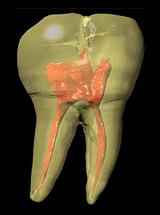

牙齿最外层叫做牙釉质,顾名思义,就是让牙齿看起来光亮洁白的一层物质。这层牙釉质是身体中最坚固的结构,比骨骼还要硬,牙釉质的96%都是矿物质,里面没有血管和神经。

从X光片上可以清楚地看到牙釉质,由于密度高,它的颜色最白

牙釉质里面包裹的是牙本质,牙本质的硬度比牙釉质低一些,里面布满了细小的管道,与最里层的牙髓相通。

牙髓是牙齿最深层的部分,里面包含大量的神经、血管和其他组织。我们之所以对咀嚼食物时的冷热酸甜有感觉,都是因为牙髓在传导这些刺激。“牙疼不是病,疼起来真要命”,这种难以忍受的疼痛就是牙髓对外界伤害的反应。

另外,牙髓还能制造外层的牙本质。如果牙齿的哪一部分遭到了损伤,牙髓可以制造一层牙本质,起到修复的作用。